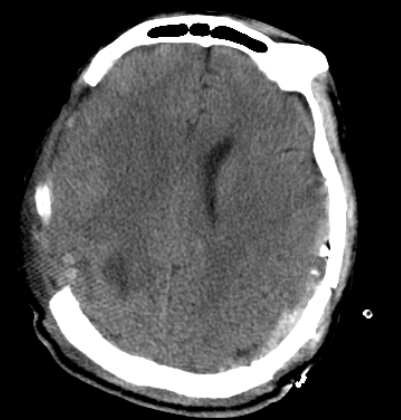

无影灯下,主刀医生赵坚柱凭借丰富的经验和精湛的技术,小心翼翼地清除血肿,细致处理骨折部位,精准进行止血操作。麻醉团队全程严密监控患者生命体征,手术护士默契配合,确保手术顺利进行。经过五个多小时的紧张奋战,手术团队成功清除了患者左侧及右侧的颅内血肿,妥善处理了颅骨骨折,彻底解除了脑组织受压状况。整个手术过程中,团队成员沉着冷静,配合默契,以专业素养牢牢守住了生命的最后防线。

复查结果显示

术后,患者在重症监护室接受了全方位的精心治疗和护理。ICU团队24小时密切监测患者病情变化,及时调整治疗方案。在医护人员的共同努力下,患者生命体征逐渐平稳,意识状态日益改善,目前恢复情况良好,不久后将转入普通病房继续康复治疗。